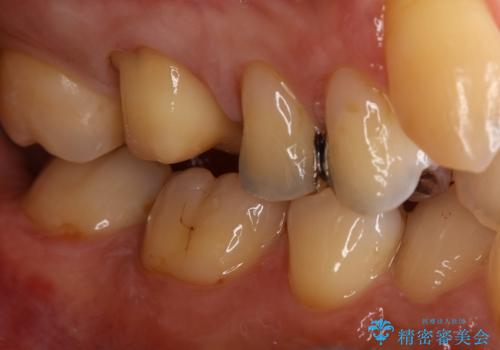

銀歯をセラミックに変えたい

- 銀歯のセラミックへのやり替えをご希望で来院されました。

銀歯が入ってる歯は複数箇所ありましたが、咬合力がより強く破折リスクが高い奥歯から治療を開始してます。